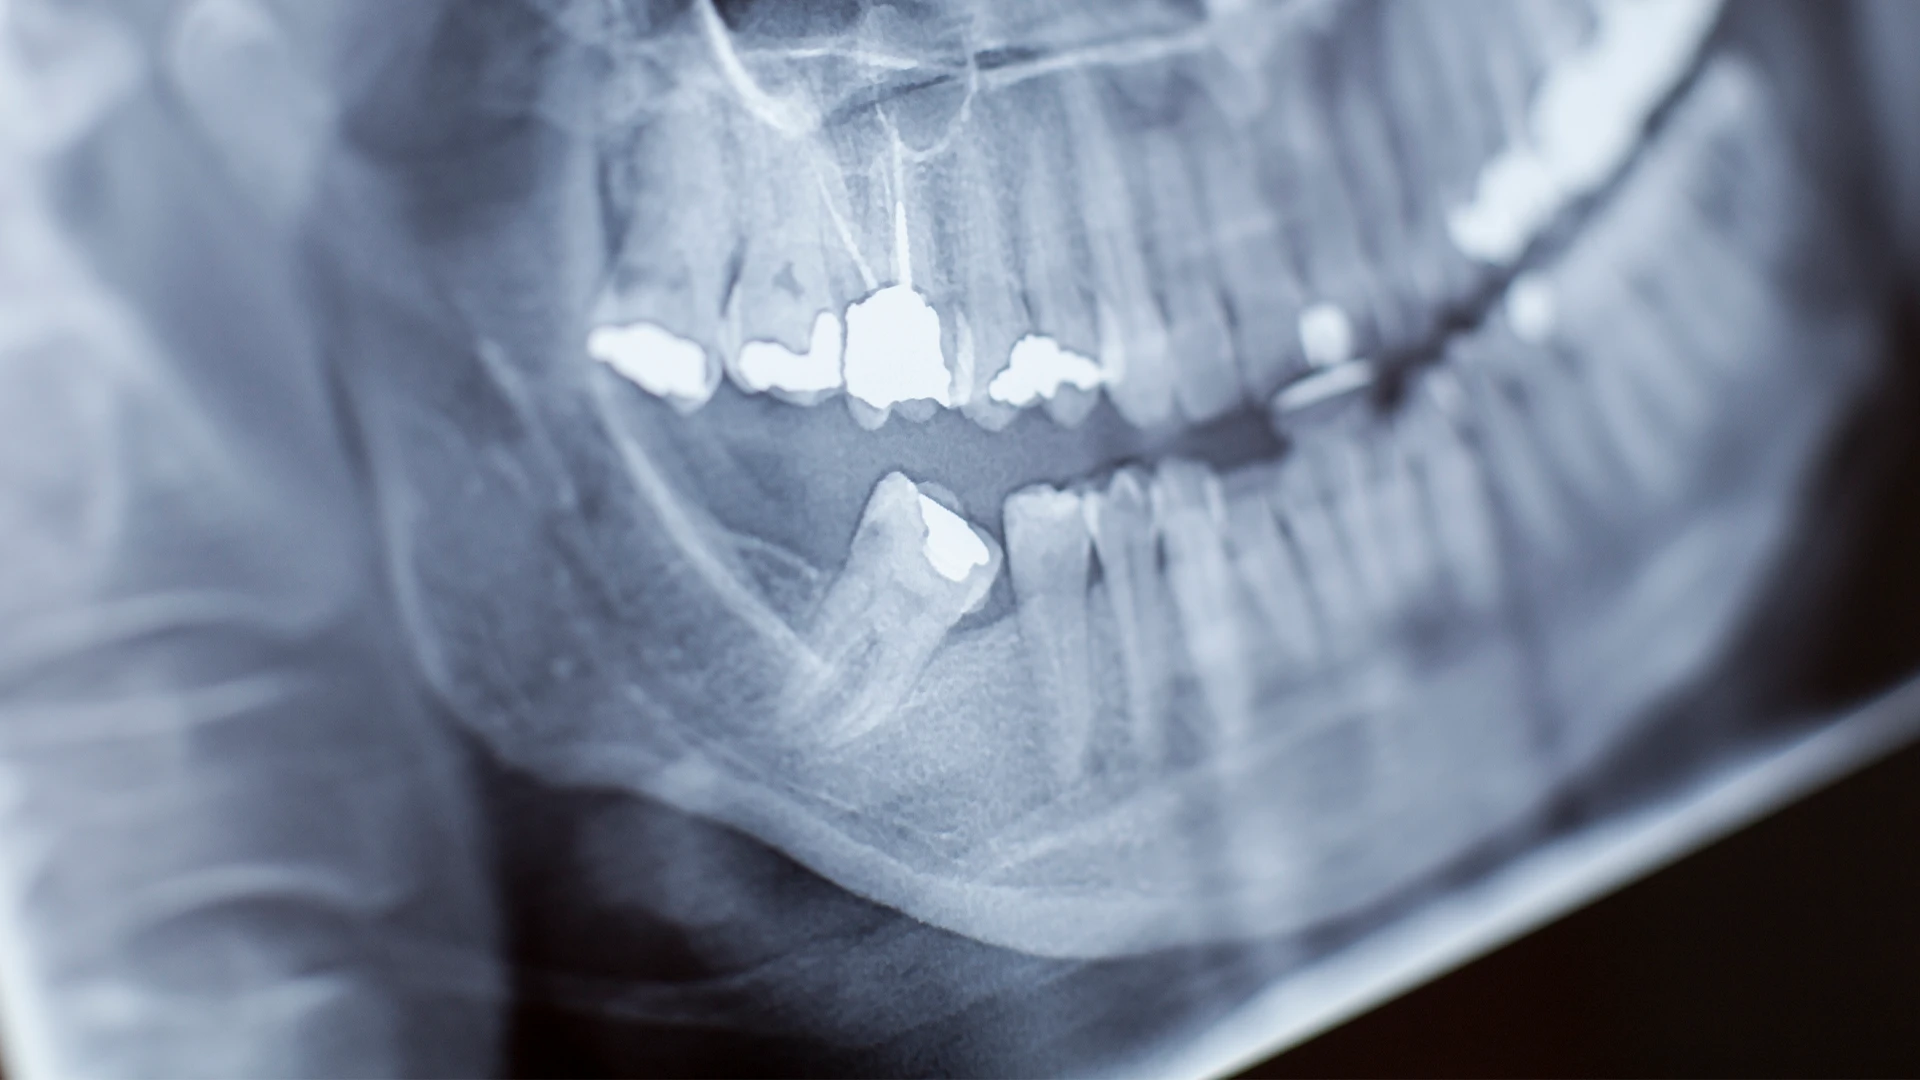

Der erste Schritt, um mit der Extraktion betroffener Zähne bei Dent Foça zu beginnen, ist die Durchführung einer umfassenden Untersuchung und Beurteilung in unserer Poliklinik. Ihr Zahnarzt erstellt den am besten geeigneten Behandlungsplan, indem er den Zustand des betroffenen Zahns und des umliegenden Gewebes untersucht. Unser Ziel ist es, die Zahnextraktion auf die bequemste und sicherste Weise durchzuführen.

Bei retinierten Zähnen handelt es sich um Zähne, die meist aufgrund von Platzmangel nicht oder nur teilweise durchbrechen können. Diese Situation tritt normalerweise bei Weisheitszähnen auf. Impaktierte Zähne können Probleme wie Infektionen, Schmerzen, Zahnfleischerkrankungen oder Schäden an benachbarten Zähnen verursachen. In solchen Fällen empfiehlt sich die Extraktion des retinierten Zahnes.

Die Extraktion retinierter Zähne wird in der Regel unter örtlicher Betäubung durchgeführt. Nachdem der Zahn und das umgebende Gewebe betäubt wurden, extrahiert Ihr Zahnarzt den Zahn mit Spezialwerkzeugen. Da die retinierten Zähne tiefer liegen, kann ein chirurgischer Eingriff erforderlich sein.